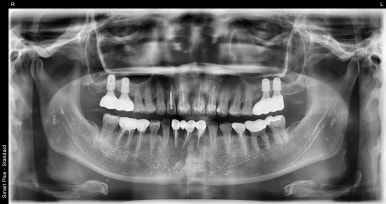

상악동거상술을 동반한 임플란트 치료 전

2022-08-23

이번에는 상악동거상술을 동반한 임플란트에 대해 설명드리고자 환자분 사례를 보여드리겠습니다.

상악동거상술을 동반한 임플란트 치료 전후

(전) 2022-08-23 (후) 2023-07-25

이번 환자분의 경우 사진상 오른쪽(실제 왼쪽) 맨끝 어금니 2개를 임플란트로 치료하신 케이스인데요.

뼈이식 6개월 후에 뼈가 단단해지는지 지켜보고 임플란트를 식립하기로 했습니다. (지연식립)

최초 뼈이식을 22년 8월 말에 진행하셨고, 임플란트 수술은 23년 2월 말에 진행하셨으니 딱 6개월 후에 임플란트를 식립하게 되신 것이죠.

임플란트를 식립하고 4개월 후에 보철물(크라운)을 올리는 계획으로 진행했는데,

3개월 후 수치 측정 결과 아직은 뼈가 단단하게 굳지 않았다고 판단해 한달 더 기다린 후 7월에 보철물을 세팅하게 되었습니다.

최종적으로 거의 1년 정도 소요되었다고 보시면 될 것 같습니다.